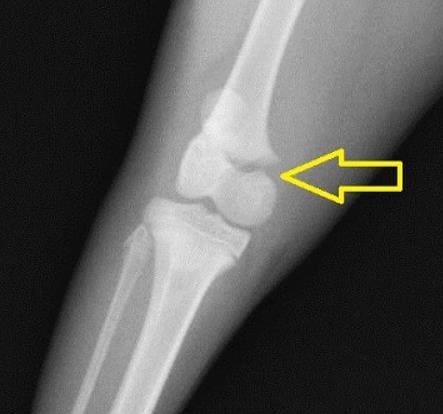

무릎뼈 확인

먼저 발이 닿지 않는 의자에 앉은 후 무릎뼈를 꾸욱 눌러보시길 바랍니다. 이때 무릎뼈와 다리 사이에 있는 연골의 있어 헷갈릴 수 있는 만큼 예민하게 살펴보시길 바랍니다.

만약 성장판이 닫힌 어른의 경우라면 말랑거리고 안으로 들어가지만 그렇지 않은 아이의 경우 조금 다른데요. 약간의 딱딱함이 느껴진다면 성장판이 아직까지 열려 있다고 생각하실 수 있습니다.